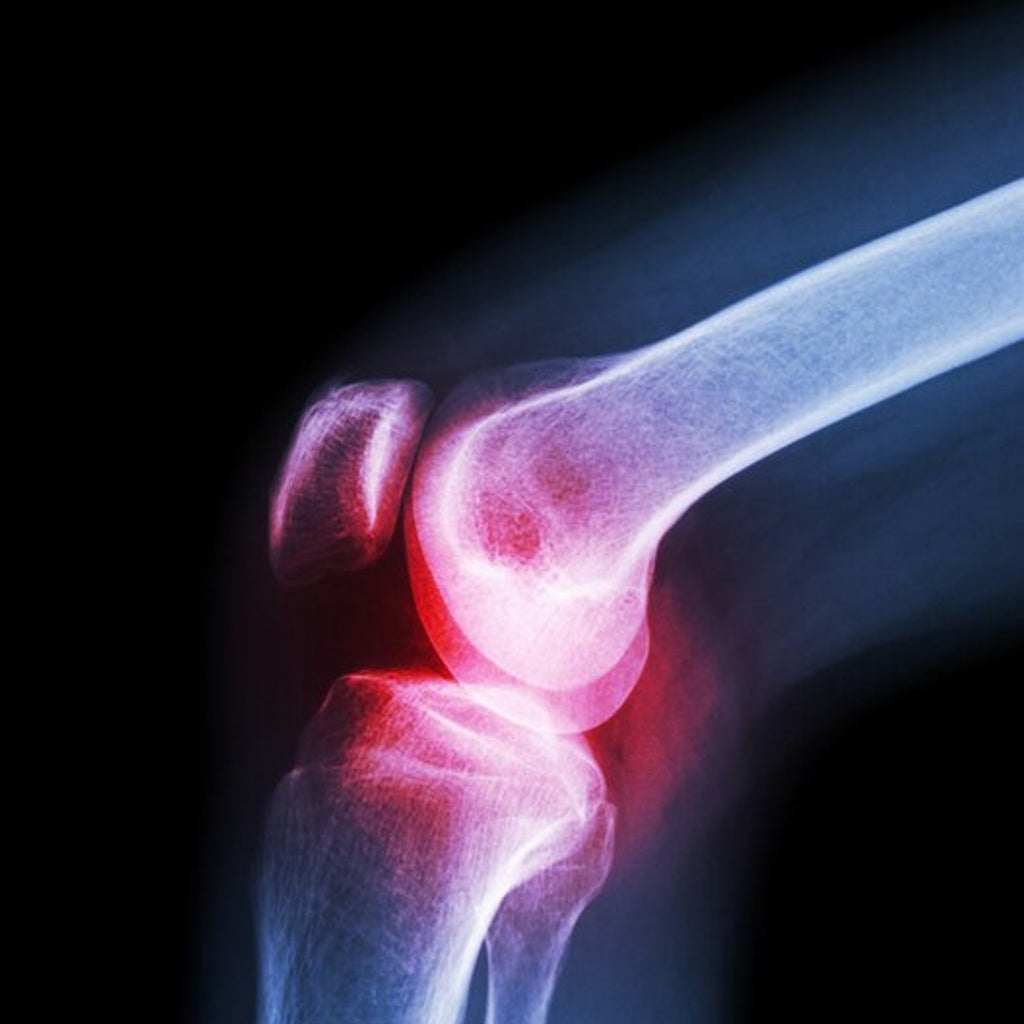

The Knee Cap provides sufficient support to the knee joint. It is designed to apply the right degree of pressure that can help reduce pain caused by osteoarthritis, osteoporosis, or an injury-triggered swelling around the knee. Because of its compression function, it can also bring relief and can help speed up recovery from any muscle or ligament injury. Since it supports the knee and protects the knee joint, it can be worn during any physical activity and reduce the risk of injuries. Knee Cap has a special knit material with two-way stretchability for easy wearing. It is made from a very breathable and comfortable material. It does not cause a foul odor due to its ability to absorb sweat.